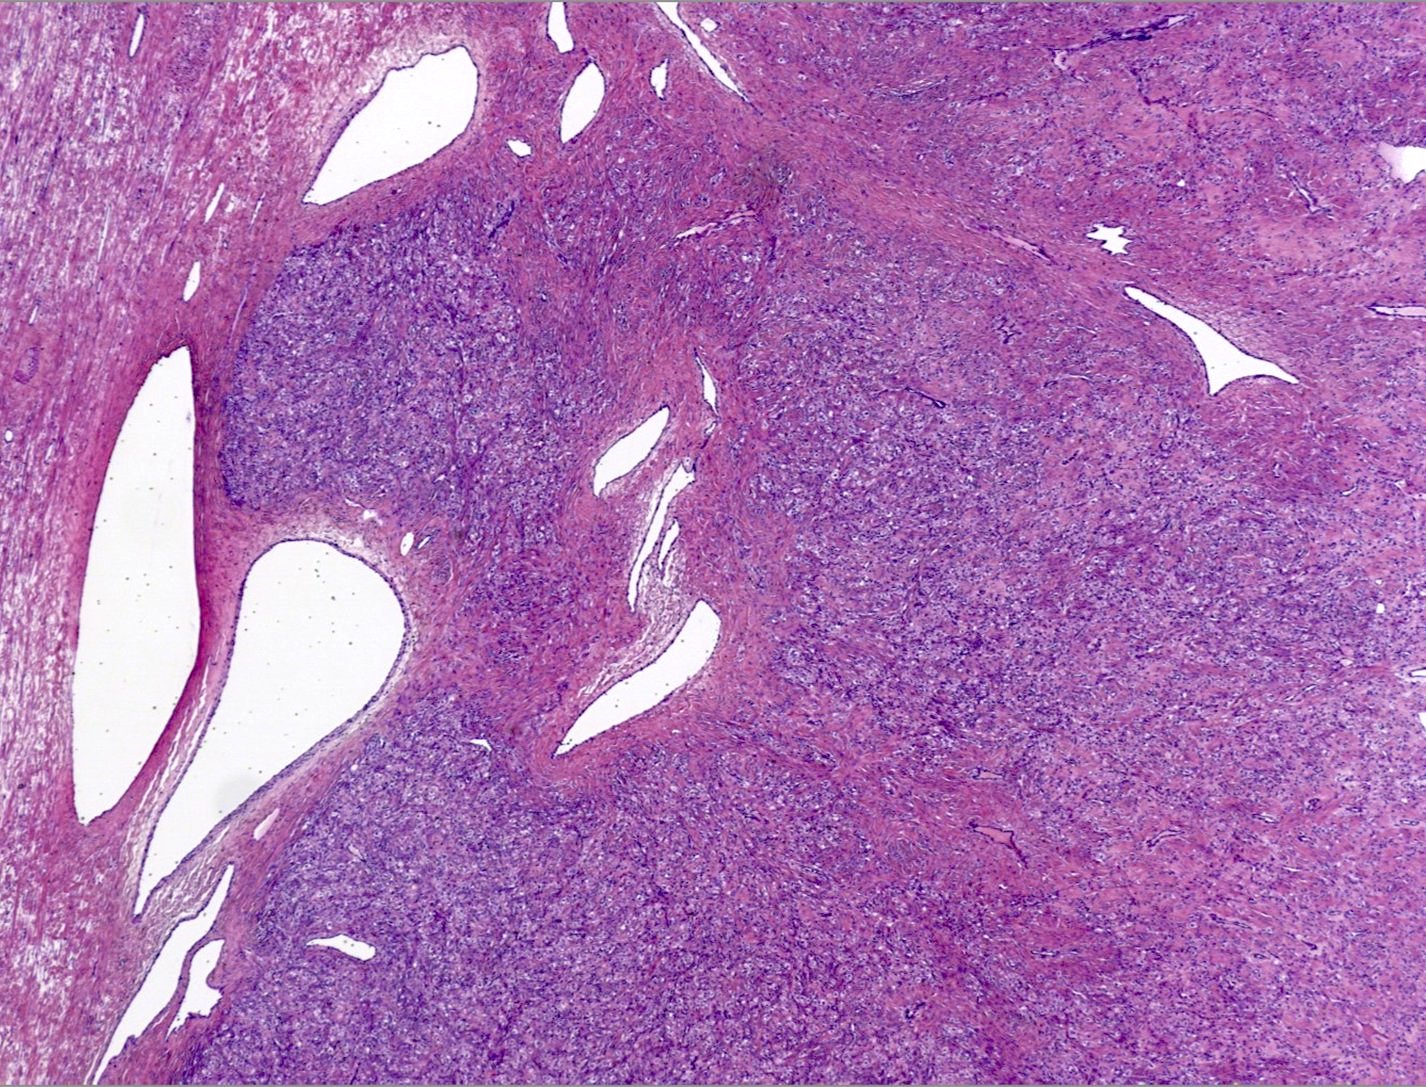

Microscopic (histologic) description

- Alternating cellular and hypocellular areas impart a pseudolobular appearance

- Thin, dilated and branching hemangiopericytoma-like vasculature is often conspicuous in both components

- Pseudolobules comprised of a jumbled admixture of epithelioid (lutein) and spindled cells with minimal atypia

- Hypocellular areas can be edematous, collagenous (variably keloid-like) or myxoid

Microscopic (histologic) images